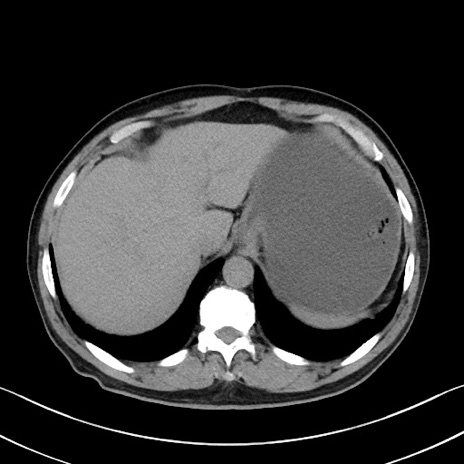

症例35(横断像)

【症例】70歳代 男性

【主訴】腹部膨満、嘔吐

【現病歴】昨日より腹部膨満感出現。本日増悪し、仙痛出現。嘔吐あり、受診。

【既往歴】糖尿病、胆摘後

【身体所見】BP 149/80mmHg、HR 74/min、BT 35.9℃、腹部:膨満、軟、圧痛なし。腸雑音減弱あり。上腹部正中切開瘢痕あり。

【データ】WBC 13500、CRP 1.72